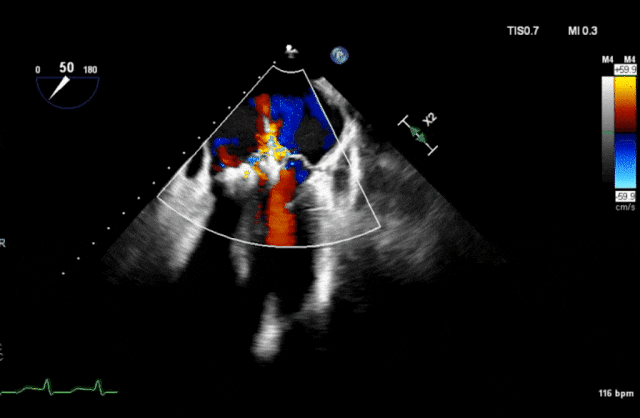

心脏超声示左室增大,二尖瓣2、3区脱垂伴重度反流(腱索断裂),Carpentier分型Ⅱ型,典型Barlow综合征表现;二尖瓣开放面积5.0cm²,3区瓣环内径31mm,前叶长22mm、后叶17mm,前叶收缩期关闭瓣体部分呈拱形突向左房腔,瓣膜游离缘对合欠佳,可见腱索断裂,长度9mm;2区瓣环内径32mm,前叶长22mm、后叶10mm,前后叶均可脱垂;三尖瓣重度反流。CDFI示瓣口重度偏心性反流,反流束沿主动脉后壁走行,肺静脉收缩期可见反向频谱。

术前反流

图片